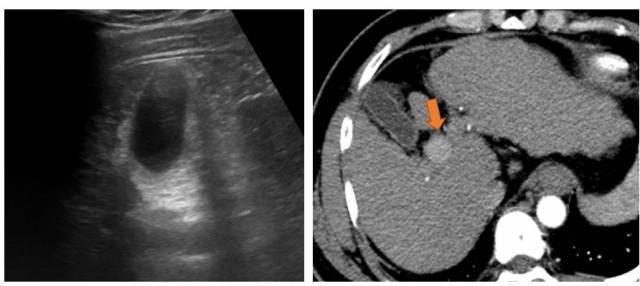

하지만 수술적 치료가 가능한 조기 간암의 경우 간초음파 검사만 시행할 경우 발견할 수 있는 확률이 절반 수준이다. 실제 간초음파 검사만으로 추적 검사를 시행할한 환자들 중 적지 않은 수가 조기 진단 되지 못하고 간암이 진행된 상태에 발견된다. 특히 비만, 알코올 섭취 등으로 지방간이 심하거나 간경화증이 많이 진행된 경우에는 초음파만으로 간 전체를 관찰하는 것이 불가능하기 때문에 간초음파의 진단 능력이 더욱 떨어진다. 간초음파 검사 대상으로 적절하지 않은 환자들의 간암 발생 가능성이 더 높은 경우가 대부분이라 더욱 문제가 되고 있다.

일본간학회는 간암 발생 가능성이 매우 높은 간경화증 환자에게 간초음파 외에도 전산화단층촬영(CT) 또는 자가공명영상촬영(MRI)을 이용한 추적 검사를 추천한다. 대한간암학회와 국립암센터 간암 진료지침에도 간암 검진 시 CT나 MRI를 이용을 고려하라고 적시되어 있다. CT나 MRI는 간암을 발견하는 능력이 간초음파보다 현저히 뛰어나다. 또한 지방간이나 간경화 정도에 따라 진단 능력이 달라지지 않고, 조직검사 없이도 간암을 진단할 수 있어 임상적으로 매우 유용하다. 물론 CT나 MRI도 단점이 있기 때문에 모든 환자들에게 추천되지는 않는다.

장단점을 종합적으로 따져보면 보통의 경우보다 간암 발생 가능성이 매우 높은 환자들은 CT나 MRI를 이용한 간암 검진을 시행해야 한다. 만성 B형, C형 간염과 함께 간경화증이 있는 경우가 대표적이다. 이런 환자들은 간암 발생 가능성이 연간 2~3%를 넘는다. 특히 간초음파에서 간 전체가 보이지 않는다면 CT나 MRI를 적극 고려해야 한다. 혈액검사에서 간암의 종양표지자가 증가된 경우도 CT나 MRI를 이용한 간암 검사의 대상이 될 수 있다.